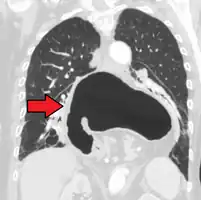

A large hiatal hernia as seen on CT imaging

A large hiatal hernia as seen on CT imaging- As seen on ultrasound[12]